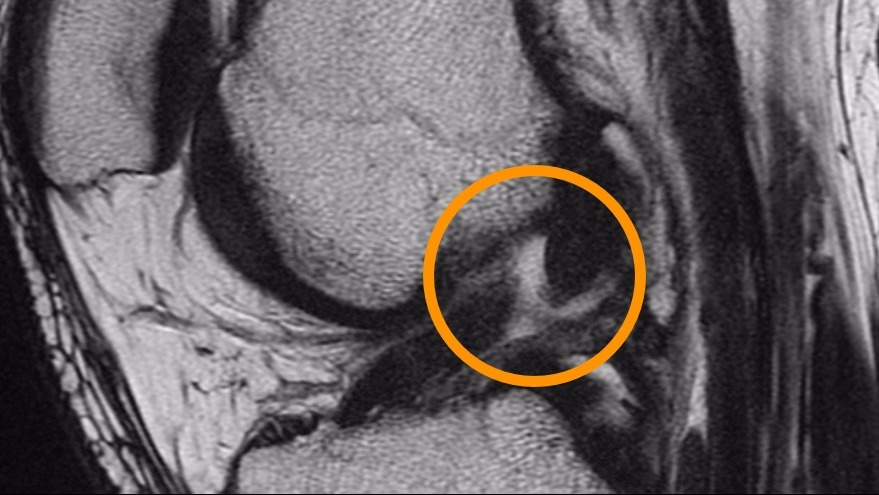

• 871965.jpeg

871965.jpeg

93.5 KB · Views: 2